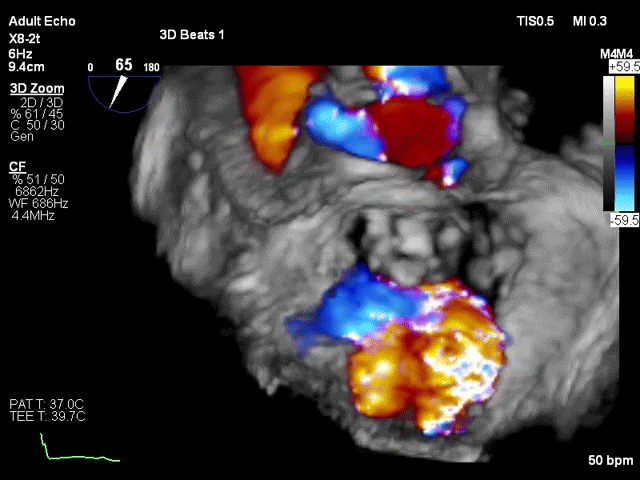

患者术后30天随访状态良好,随访显示左心室逆重构,左心室功能伴左心室结构显著改善,全面达成包含二尖瓣反流程度降低、心功能改善等有效性指标。人工二尖瓣工作正常,支架结构及形态稳定,锚固良好无位移,无瓣周漏。瓣叶开闭形态良好,血流动力学表现优异,平均跨瓣压差仅1mmHg。

该手术采用左侧第五肋间微创切口心尖入路,透视下经导丝置入输送系统,逐步释放瓣膜。透视及TEE确认瓣膜位置满意后撤出输送系统,二尖瓣瓣膜形态及工作状态良好,复查左心室造影,提示无瓣周漏,无左室流出道梗阻,左右冠状动脉显示良好,未受任何影响。

该患者已顺利完成30天随访,恢复状态良好,随访结果显示患者心功能改善明显,瓣膜工作正常,瓣叶开闭形态良好,无瓣周漏,无左室流出道梗阻,标志着这款完全由心通医疗自主研发的经导管二尖瓣置换系统首例应用取得成功,顺利进入临床试验阶段。该临床试验已获中山医院医学伦理委员会批准。